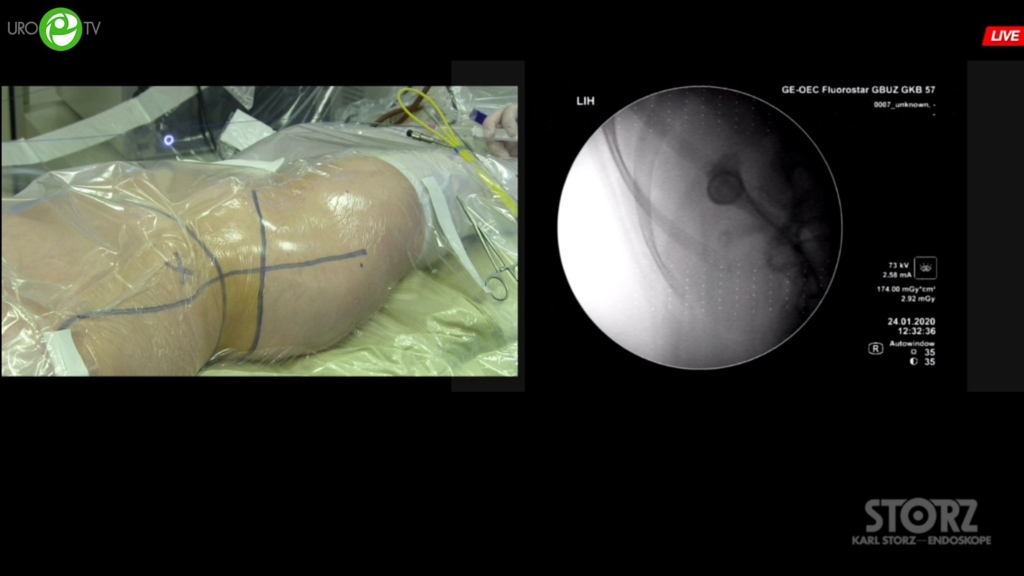

Мартов А.Г. - Мини-перкутанная лазерная нефролитотрипсия

07 мая 2020

Мочекаменная болезнь